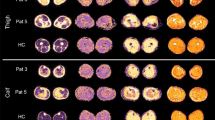

qMRI outcome measures in ICU survivors compared to controls

Water T2 mapping sequence was acquired for 5/9 patients due to a change in examination protocol (see methods). Example images of the applied MRI sequences are shown in Fig. 1. The average qMRI values were significantly higher in all patient muscles compared to controls (multivariate general linear model: main effect: p < 0.001 for water T2, FF, MD, λ1, RD; p-value for FA was 0.047; see Table 3). The mean qMRI values of all muscles combined for patients and controls are displayed in Fig. 2. For complete qMRI data see Table S1.